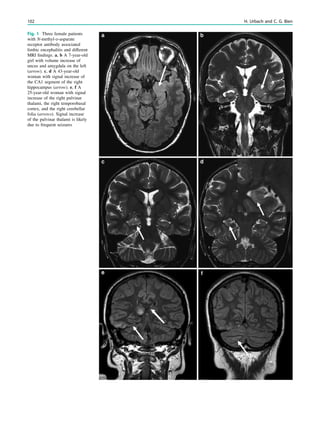

Fig. 1 Digital photogram of the brain surface before placement of a

Fig. 2 Epileptogenic lesion and symptomatogenic zone. A 40-year-

(a, arrow). Simultaneous video and EEG recordings from interhemi-

Clinical symptoms start around 1 s afterwards (d, asterisk)